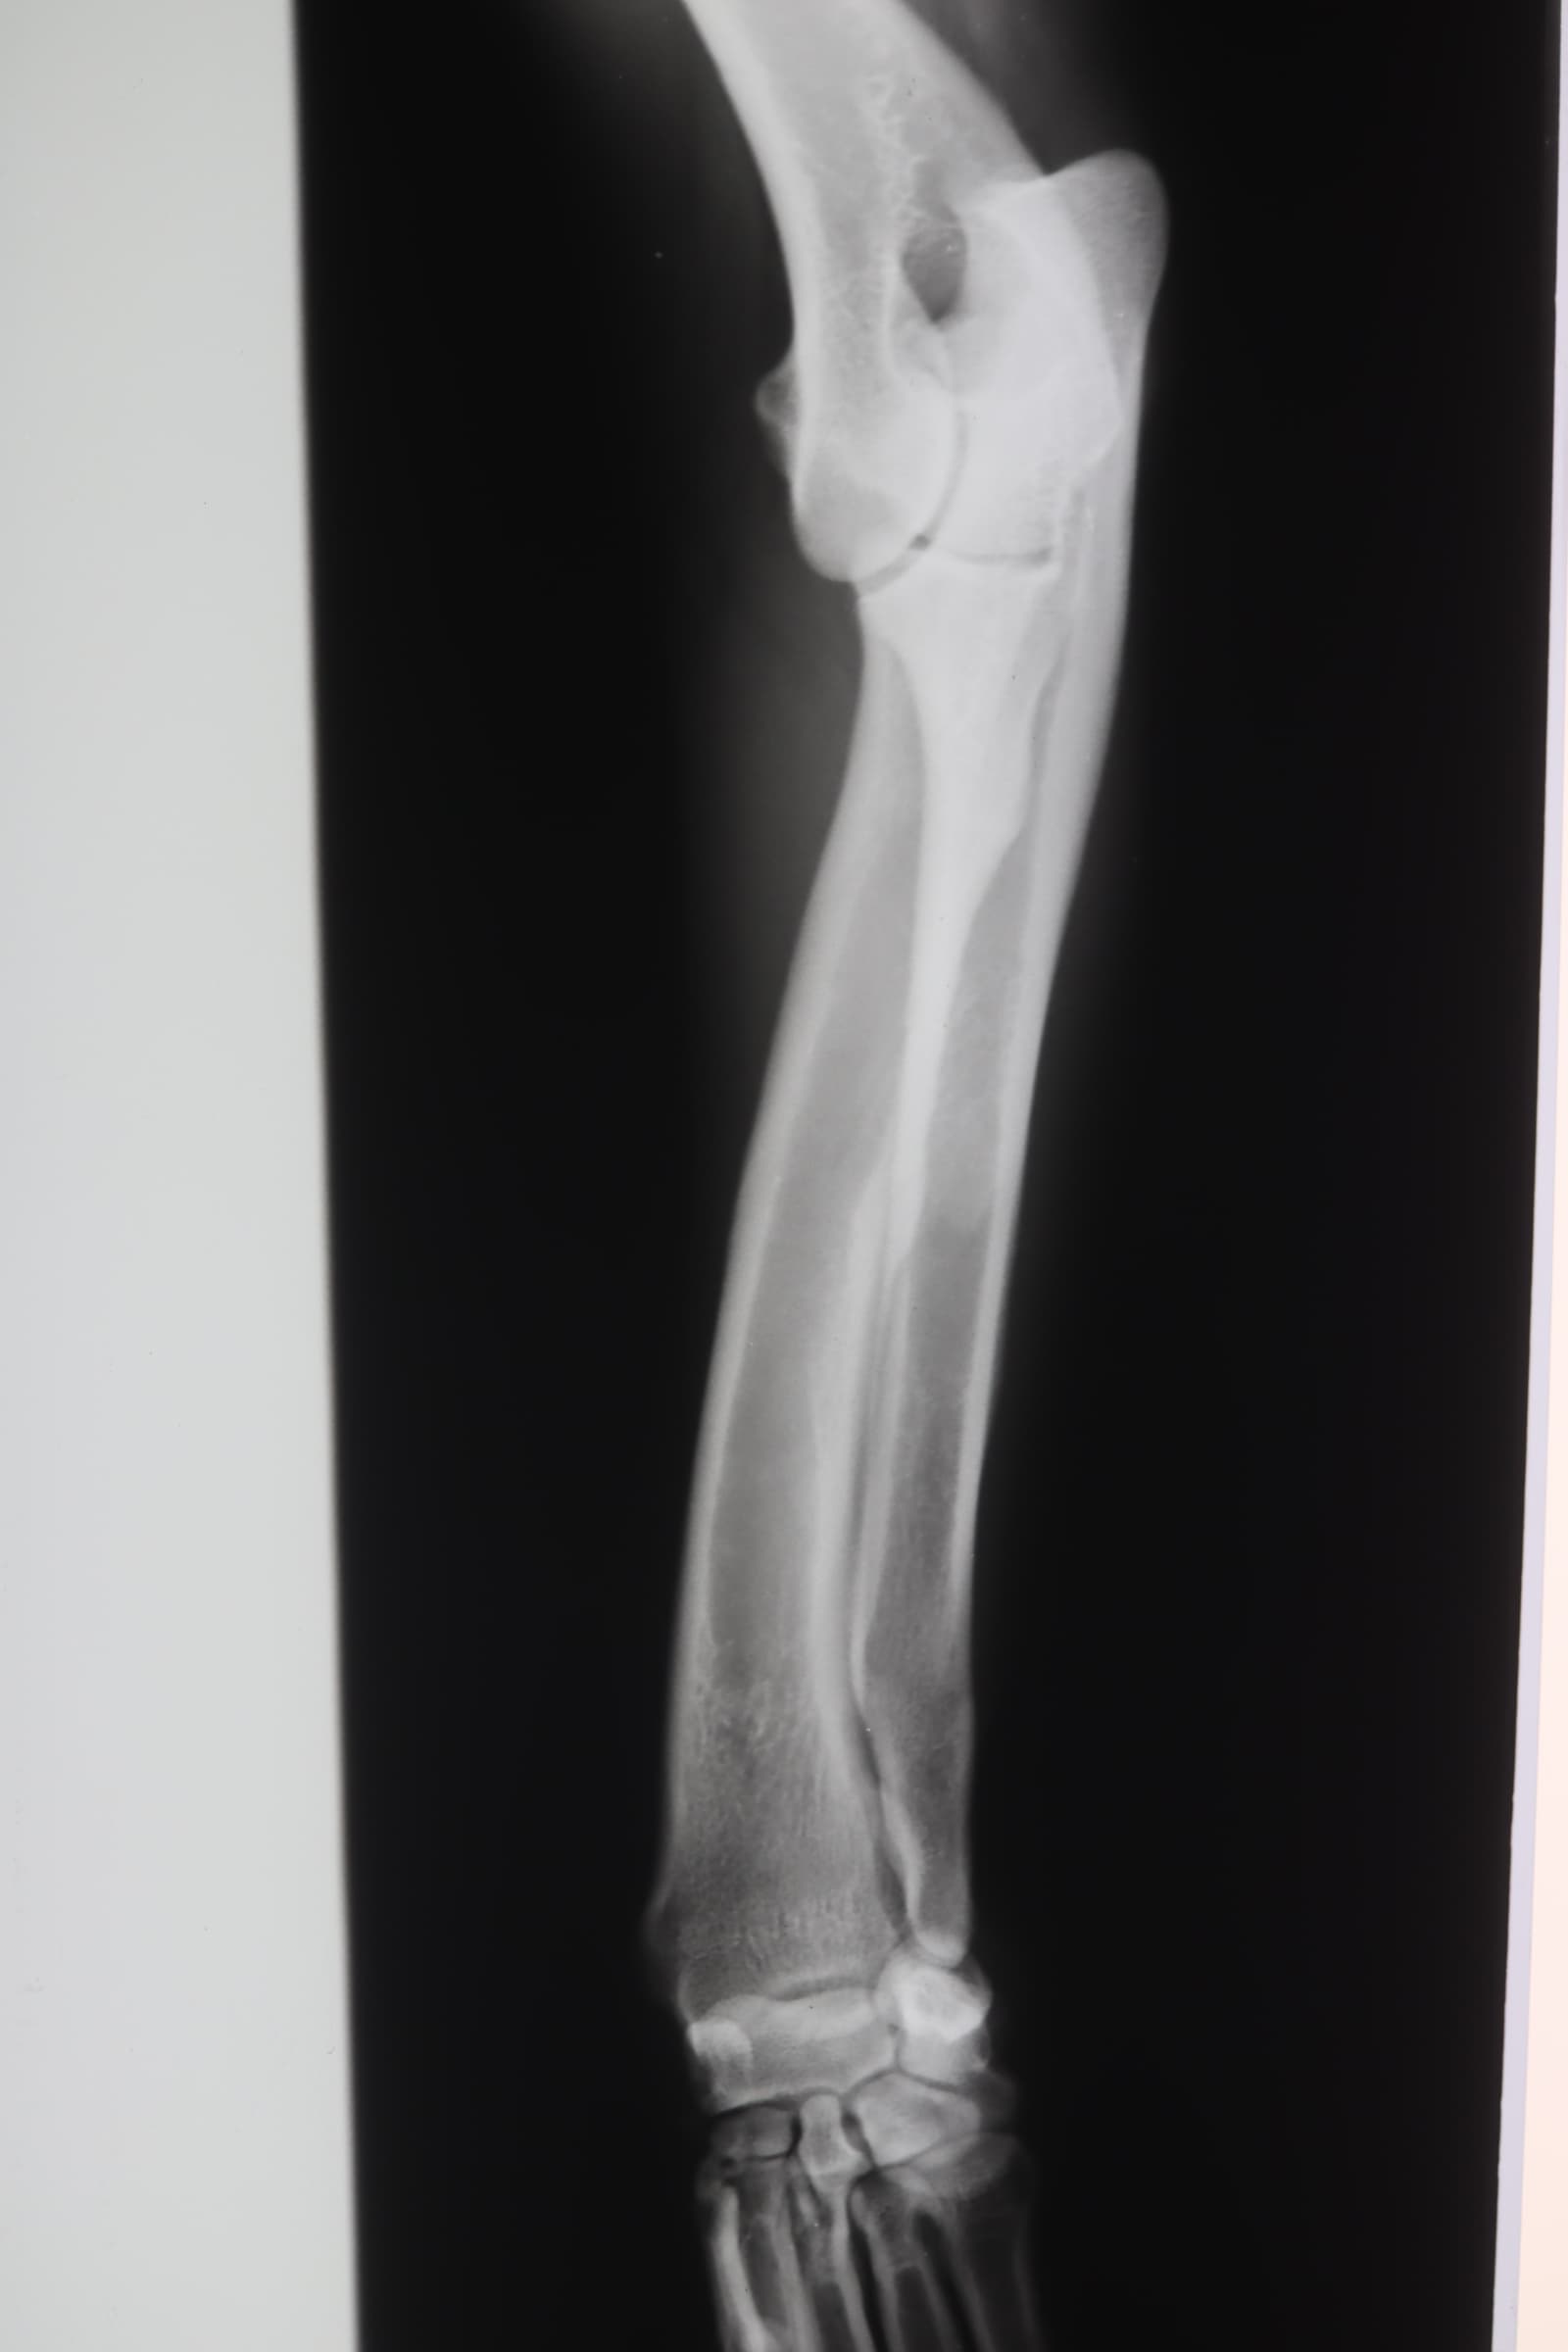

レントゲン検査

前足が曲がっているためレントゲン検査をしました。おそらく、子犬のときに足を痛めた影響で、二本の骨の一本ががうまく成長しなかったようです。

痛めた方はの骨が成長の衰え、一方は正常に成長しようとするので、足が曲がってしまっています。幸いなことに、それは軽度なので、症状があまりありません。重症な場合は、肘関節が外れてしまうことがあります。(2024年10月24日)